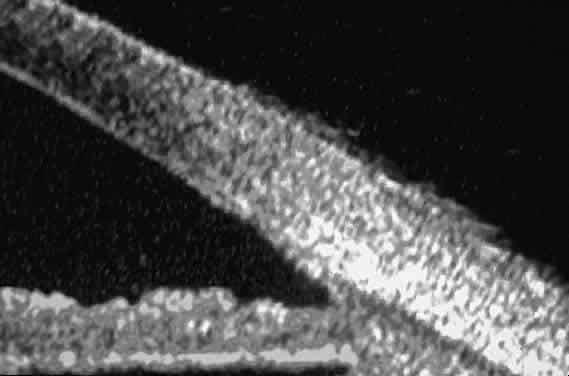

The role of UBM in the preoperative assessment of eyes with cataract is as yet unknown. In certain eyes, however, UBM may reveal features or abnormalities that could alter the ophthalmologist's surgical approach. Postoperatively, UBM can show the size and location of an intraocular lens (IOL) and the positioning of the haptics. A posterior chamber IOL appears on UBM as a highly reflective plate (corresponding to the lens optic) in the retropupillary plane with reverberation artifacts behind it (Fig. 17A). In contrast, an anterior chamber IOL appears on UBM as a sonoreflective plate located anterior to the pupillary plane (see Fig. 17B). In most eyes with a posterior chamber IOL, UBM can show whether the haptics are in the capsular bag (Fig. 18A), in the ciliary sulcus (see Fig. 18B), or in some other anatomic location12 (e.g., resting on the peripheral iris or secured with sutures to the sclera). The haptics are easier to locate if they are made of polymethyl-methacrylate than if they are made of proline because the former has a stronger reflectance.